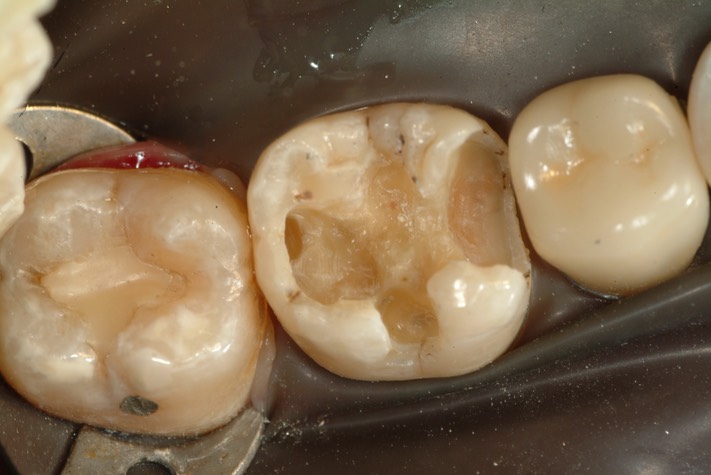

Larry Fujioka #30 amalgam removal